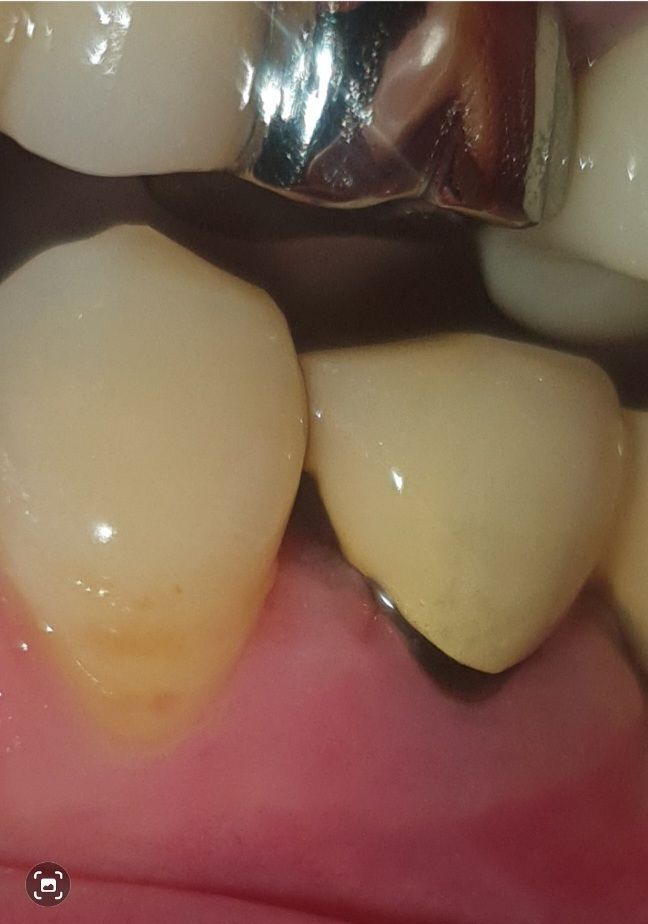

치주염 치과의사 선생님 계실까요~?

다름이 아니오라 예전에 신경치료후 크라운으로 덮어 씌웠습니다.

하지만 앞자연치아의 공간 사이와 크라운치아가 조금 벌어져있게 제작되었습니다.

그래서 저 사이의 공간이 좀 있는편이라 거기에 음식물 찌꺼기가 많이 끼는 편입니다.

이에 치실을 하루 한번 하는편인데, 잇몸이 조금 내려가는 기분이 들어서 이렇게 사진을 올리게 되었습니다.

혹시 치주염인지 봐주실 치과의사 선생님 계실까요..? ㅠㅠ..

• 4번 째 사진

해당 부위에서 출혈이나 농이 나온다면 치주염을 의심해볼 수 있습니다. 잇몸에 붓기 등은 있어보입니다.

보철물을 만들떄 무조건 치아 사이를 완전히 메꾸는건 아닙니다. 아마 처음에는 저정도 공간은 아니엿지만 시간이 지나면서 잇몸이 내려가면서 공간이 더 넓어진거 같습니다.

현재로써는 잇몸이 많이 내려와 있어보이지는 않으나, 이 공간이 음식물 찌꺼기로 인해 염증을 유발될수 있습니다.